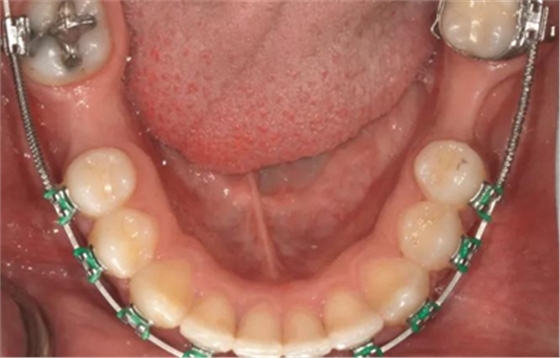

經(jīng)過(guò)最初1年的正畸排齊后,右側(cè)下頜第一磨牙無(wú)牙區(qū)的近遠(yuǎn)中距離由6mm增至7mm,左側(cè)下頜第一磨牙的近遠(yuǎn)中距離由7mm增至8mm(圖4)。取得患者知情同意后,采用與病例1中描述的相同技術(shù)和材料進(jìn)行同期牙槽嵴增量和加速磨牙直立程序(圖5a-5g)。除了右側(cè)磨牙后區(qū),在右側(cè)第二和第三磨牙根部之間也進(jìn)行了去皮質(zhì)術(shù)(圖5d)。骨增量術(shù)后,即刻將0.016×0.022 英寸帶有30° 后傾彎的鈦鉬合金絲(Dentsply)置于兩側(cè)。6周后,以半個(gè)托槽的距離進(jìn)行主弓絲套推簧雙側(cè)輕加力(圖5h)。

術(shù)后3個(gè)月,右側(cè)第一磨牙的空間約為9mm(3個(gè)月中增加了1.6mm),逐漸接近了對(duì)側(cè)第一磨牙的空間(也約9mm)(圖6a)。術(shù)后7個(gè)月的錐束CT顯示,右側(cè)第一磨牙區(qū)域獲得了2.5mm的水平骨增量(圖6b 和c)。左側(cè)第一磨牙的無(wú)牙區(qū)保持相同的尺寸,在種植體植入前也需要骨增量。

圖6a.病例2中,右下第一磨牙種植位點(diǎn)獲得了成功的骨增量和加速磨牙直立。治療3個(gè)月后,第一磨牙種植位點(diǎn)增加了1.6mm 的近遠(yuǎn)中修復(fù)空間,并獲得了顯著的骨增量。對(duì)側(cè)位點(diǎn),左下第一磨牙,仍需要在種植體植入前進(jìn)行額外的骨增量